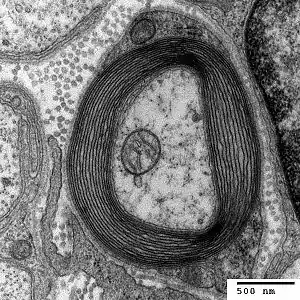

| Nerve with myelin sheath | |

HNPP is caused by a mutation in the gene PMP22, which makes peripheral myelin protein 22. This protein has a role in the maintenance of the myelin sheath that insulates nerves, resulting in insufficient conductivity in the nerves. HNPP is part of the group of hereditary motor and sensory neuropathy (HMSN) disorders and is linked to Charcot–Marie–Tooth disease (CMT).[5]

The condition is caused by a mutation in one copy of the gene PMP22 (peripheral myelin protein 22, located at locus 17p11.2). This makes it autosomal dominant.[7] PMP22 is involved in maintaining the myelin sheath that surrounds nerves to facilitate conductivity.[5] The mutation causes haploinsufficiency, where the activity of the normal gene is insufficient to compensate for the loss of function of the other gene.[8]